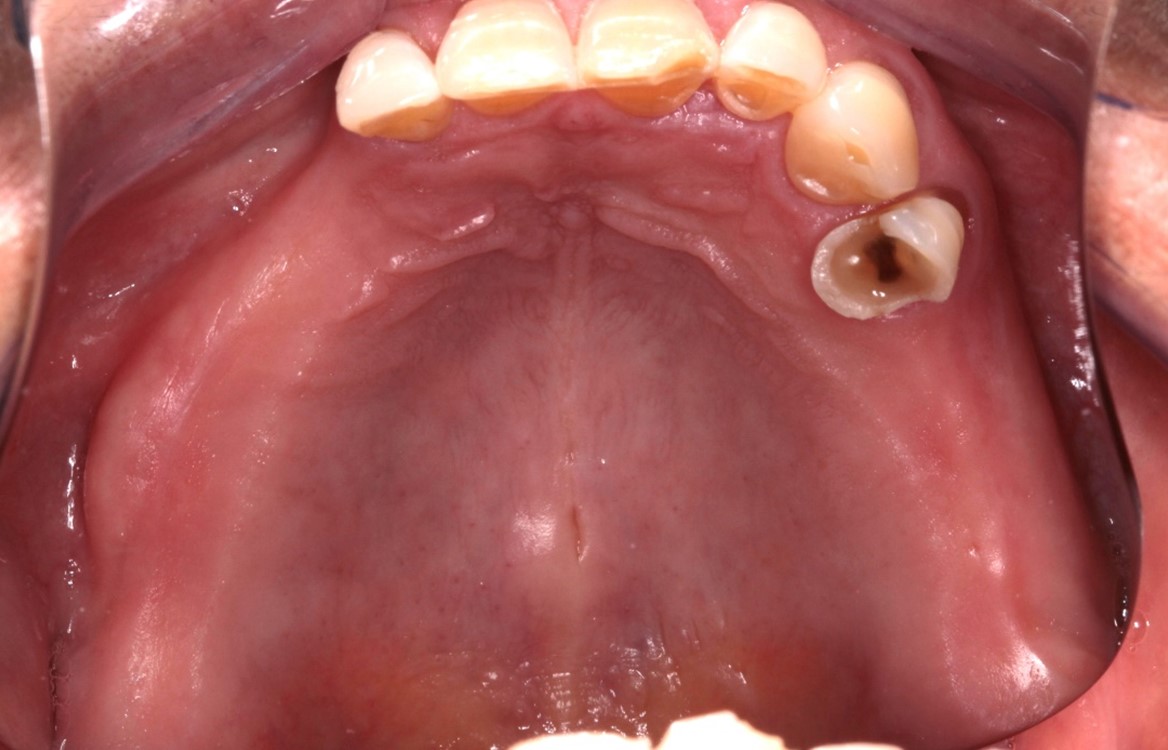

Fig. 1 e 2 – Vista oclusal

QUEIXA PRINCIPAL: O paciente relatava incômodo estético e funcional em relação ao sorriso, associado a uma sensação persistente de baixa autoestima. Mesmo após o uso de diversas próteses móveis, continuava apresentando desconforto gengival e dentário, o que dificultava sua adaptação e impactava a qualidade de vida.

Após a realização da anamnese clínica e da verificação do estado de saúde geral do paciente, foi constatado que ela se encontrava na classificação ASA 1, o que indicava um bom prognóstico cirúrgico. Durante uma conversa de orientação, foi sugerida a reabilitação com implantes unitários, destacando as vantagens desse tipo de tratamento. No entanto, o paciente demonstrou falta de aceitação em relação ao número de cirurgias necessárias para enxertos ósseo e ao tempo prolongado para a resolução do caso. Diante disso, foi proposta a reabilitação por meio de uma prótese tipo protocolo, utilizando a técnica All-on-4.

Essa abordagem oferece a possibilidade de carregamento imediato, com a instalação de uma prótese fixa em poucos dias. Apesar de estar ciente das vantagens de preservar os dentes remanescentes, o paciente optou por essa solução devido ao menor tempo de tratamento e à previsibilidade do resultado, que consiste na extração de todos os dentes remanescentes e instalação de implantes utilizando a técnica All on 4.